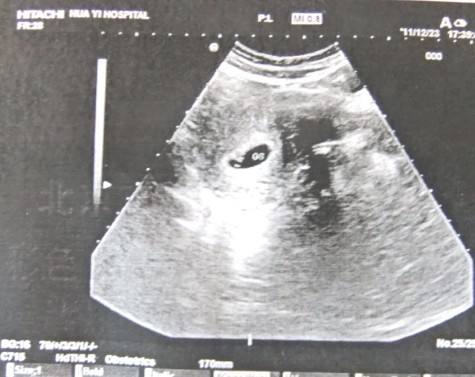

所謂的孕囊其實就是胎盤的初期階段,屬于胎盤的組織,前身,真正的胎盤是由孕囊發(fā)育而成的,在子宮內(nèi),被血管網(wǎng)和羊膜包圍著。一般通過B超查驗女人是否懷孕,只要發(fā)現(xiàn)了孕囊,且位置在子宮內(nèi),那么就可以判定女人懷孕。并且可以根據(jù)孕囊的大小,來判定出女人的孕周為多少。

在懷孕40-45天的時候,就可以聽到胎心,見到胎芽了,這時候胎囊的直徑一般為1cm大小。此時的胎兒還沒有成形,但是五官卻已經(jīng)有了顯現(xiàn),而鼻子也已經(jīng)開始在執(zhí)行功能了,那就是感知外界的氣味。

而在懷孕45天的時候,孕囊可以長到1.5cm。如果孕婦的檢查結果小于這一標準,那么就需要查明原因,有可能胎兒因為某種原因已經(jīng)停止生長了。